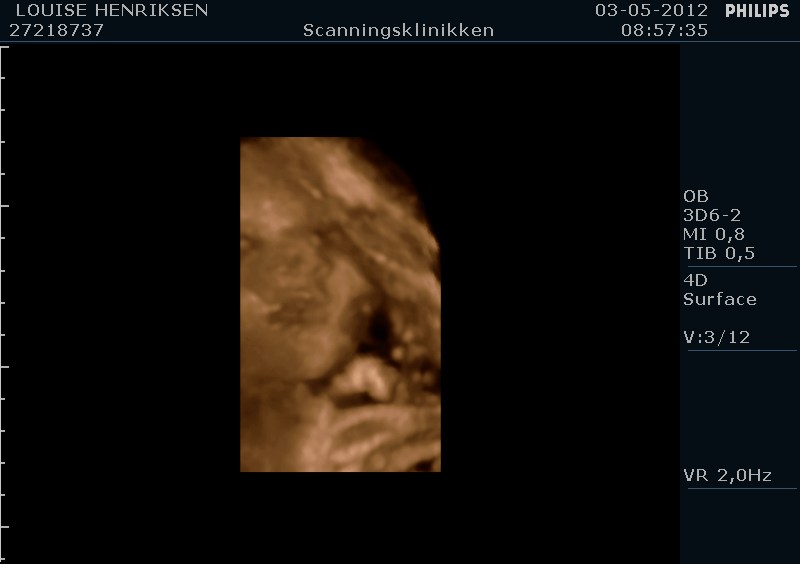

I dag skulle manden overraskes med en 4 d scanning.... og hans far var også med det var også en overraskelse, samt den lille prins....han fik bind for øjene og vi kørte mod scanning klinikken.... vi fik nogle gode sekvenser af bettemanden.. men han fylder en del derinde nu, så billederne blev ikke voldsomt gode.. men nogle fik vi dag...jeg skulle i morgen være 32 fulde uger.. mne scanningen i dag vidste34+4 dage yiarks.... jeg skal til at være færdig med den bachelor..... han vejede efter målene 1871 gram.....

så han var en fin basse...